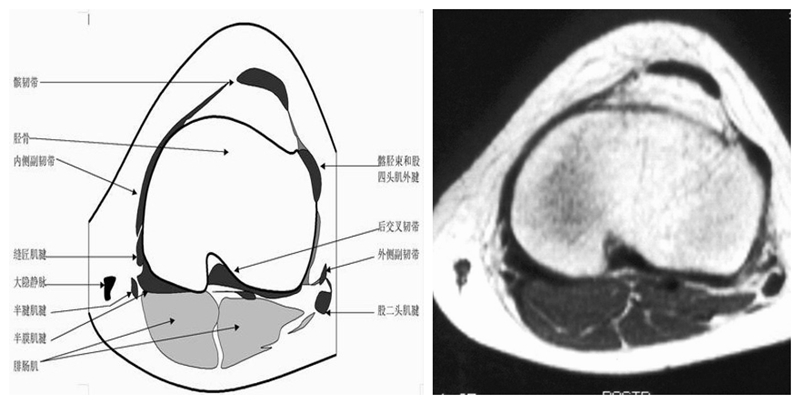

膝关节横断面MRI解剖

三维影像首选的方位,便于与CT比较,可准确地展现髌骨内外侧关节面。

横断面解剖第三层